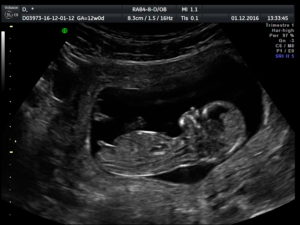

Нормы КТР

Копчико-теменной размер или сокращенно КТР — максимальное расстояние, которое можно измерить от головы до копчика на 10-14 неделе. КТР является наиболее точным параметром для определения срока беременности. В норме он должен быть от 51–59 мм.

Нормы БПР головы ребенка

Би-париентальный размер (или БПР) позволяет определить величину головы, а значит, и уровень развития мозга ребенка. БПР – это ширина головы, измеряемая по малой оси, от виска до виска. В норме должен быть 21 мм.

Размер шейной складки, или ТВП

Толщина воротникового пространства (или шейной складки) у ребенка должен быть от 1,6 до 2,5 мм.

УЗИ при таком сроке может проводиться обычным и влагалищным датчиком и помогает определить в 12 недель беременности размер плода, пол ребенка, измерить все основные показатели. Немаловажный момент: определение точной даты родов. В 12 недель беременности фото УЗИ покажет вам не зародыш, а уже маленького человечка.

Обязательно измеряется копчиково-теменной размер плода – расстояние от копчика до темени в момент максимального разгибания младенца. Это измерение проводится в сагиттальной плоскости, которая делит организм на две равные половины.

- копчико-теменной размер (КТР) — это размер, который равен отрезку проведенного от самой высокой точки теменной кости до самой дальней точки на копчике. Равен он в среднем 4,3-7,3 см.

Отдельно стоит выделить такой показатель, как размер воротникового пространства. Он важен в диагностике грубых хромосомных заболеваний. Ярким примером является синдром Дауна. В норме этот параметр не должен превышать 2,7 мм. В среднем же параметр находится в пределах 1.6 мм.